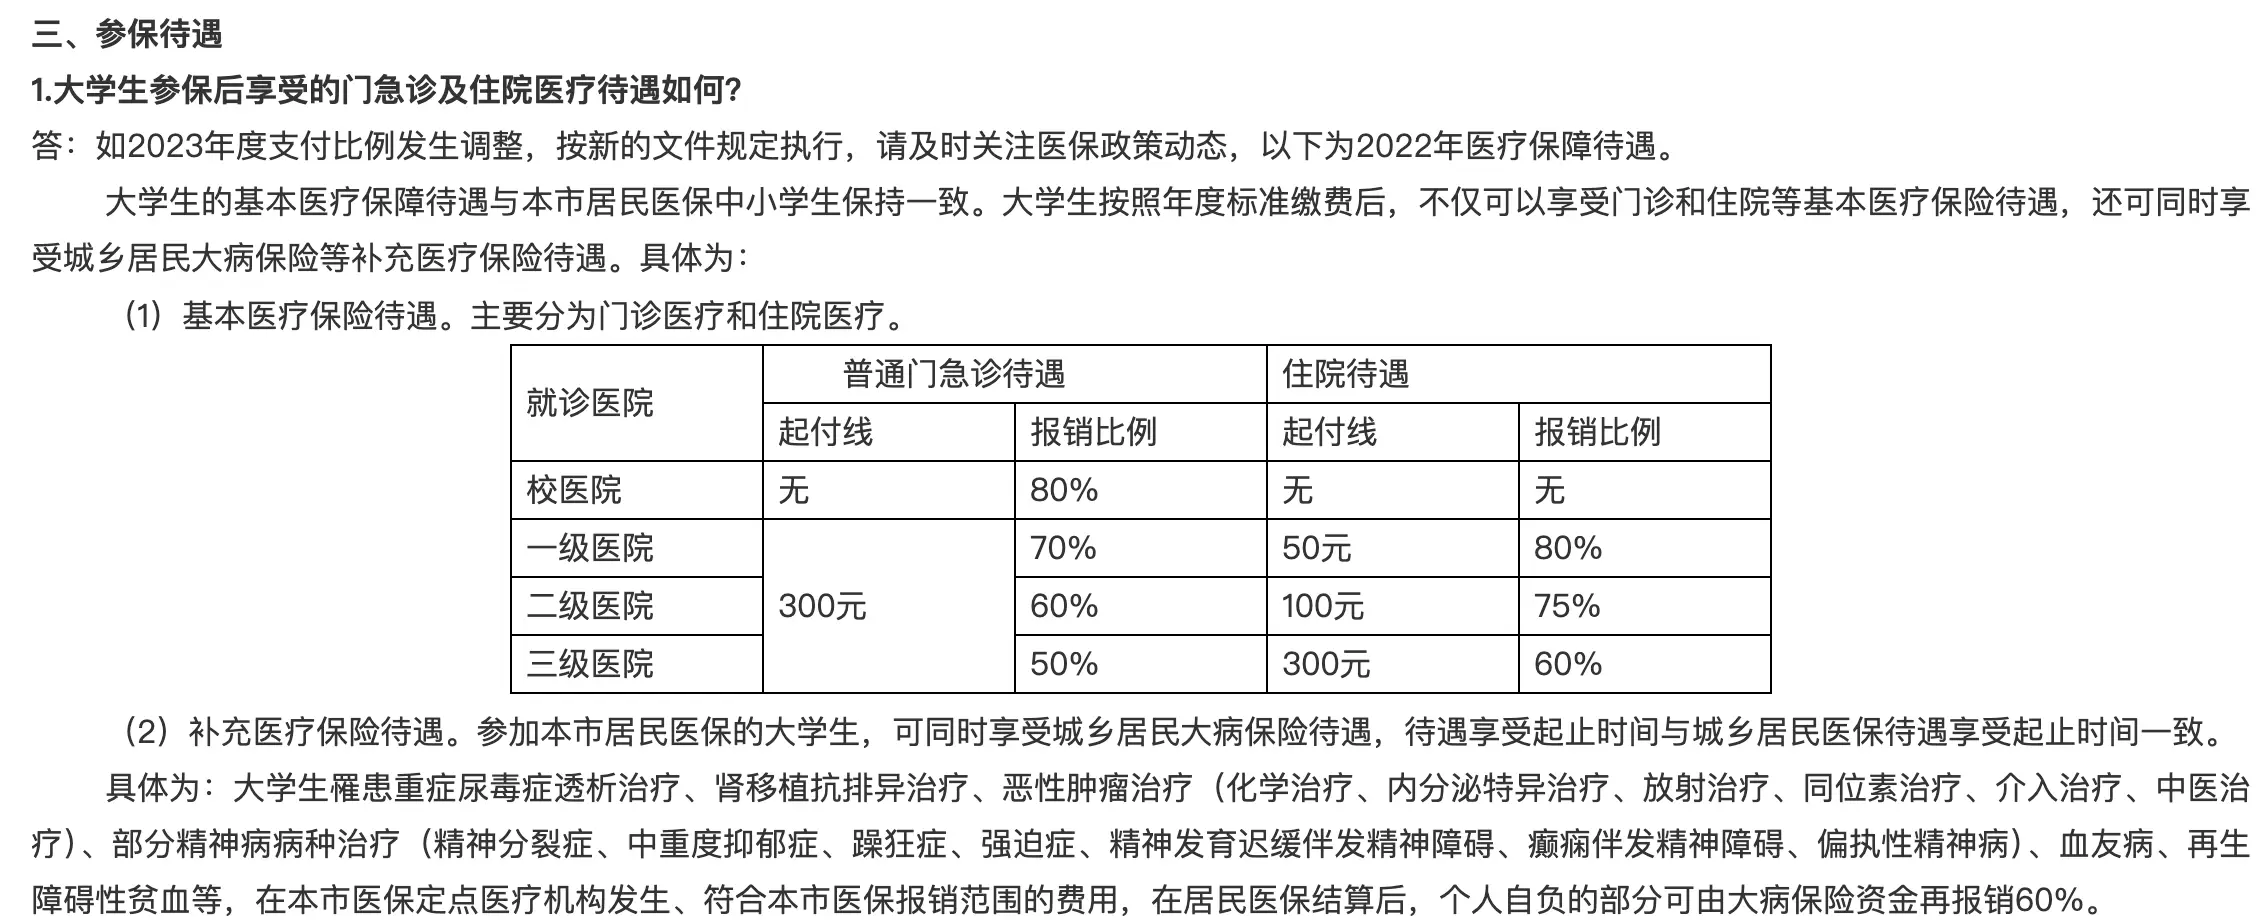

医保尚未到达起付线,微信支付了200多现大洋。

本次门诊终于到达了医保的起付线,账单是900¥多:

微信支付409¥现大洋就搞定了。